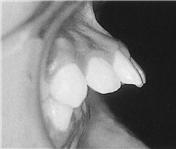

ÈçÈ÷ ¡®¹«ÅΡ¯¼ºÇâ À̶ó°í ¸»ÇÏ´Â II±Þ ºÎÁ¤±³ÇÕÀº À§Åΰú Ä¡¿¿¡ ºñÇØ »ó´ëÀûÀ¸·Î ¾Æ·¡Åΰú Ä¡¿ÀÌ ÈÄÅðµÇ¾î ÀÖ´Â °æ¿ìÀÔ´Ï´Ù(±×¸²1-C, ±×¸²2). ´ë°Ô À¯ÀüÀÇ ¿µÇâÀ» ¸¹ÀÌ ¹Þ°Ô µË´Ï´Ù.

¾Æ·¡ÅÎÀÌ ÈÄÅðµÈ II±Þ ºÎÁ¤±³ÇÕÀÇ °æ¿ì Èıâ È¥ÇÕÄ¡¿±â¿¡ Ä¡·áÇÏ´Â °ÍÀÌ ÁÁÀ¸¸ç Ä¡·É(dental age)»Ó¸¸ ¾Æ´Ï¶ó ¼ºÀåÆÇ °Ë»ç¿¡ ÀÇÇÑ °ñ·É(skeletal age), ¼ºÀû¡ÈÄ µîÀ» Âü°íÇÏ´Â °ÍÀÌ ¹Ù¶÷Á÷ÇÕ´Ï´Ù(±×¸²3). À̴ Ű°¡ ¸¹ÀÌ ÀÚ¶ö ¶§ ÅÎÀÇ ¼ºÀåµµ Ȱ¹ßÇØ Ä¡·áÈ¿°ú°¡ ÁÁ±â ¶§¹®ÀÔ´Ï´Ù. ÇÏÁö¸¸ ½ÉÇÑ °ñ°Ý¼º ¹®Á¦°¡ ÀÖ´Â °æ¿ì È¥ÇÕÄ¡¿±â Ãʱ⿡ Ä¡·á¸¦ ½ÃÀÛÇϱ⵵ ÇÕ´Ï´Ù.